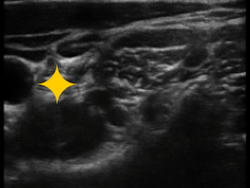

收入病区并完善相关检查后,张韶南副主任医师患者先进行“超声引导下选择性颈神经根阻滞”以缓解疼痛症状,经过治疗当天晚上患者便睡了整夜的安稳觉。后经过相关检查后,患者C6水平颈髓出现了明显的水肿信号,为积极镇痛治疗,恢复神经功能,避免出现肌力进一步下降,排除各项禁忌症后,科室专家团队在超声引导下行“脊髓神经根脉冲射频术+形状神经节阻滞术”,治疗后疼痛基本消失,手指和上肢的运动功能也恢复正常,目前该患者已康复出院。

仅仅采用一根粗细约0.7mm的“细针”,在超声或DSA下实时引导穿刺针直达病变神经节位置,对神经进行电刺激,促使神经功能恢复,达到治疗疼痛的目的。优点是对神经纤维结构无破坏作用,能有效缓解疼痛,提高生活质量。